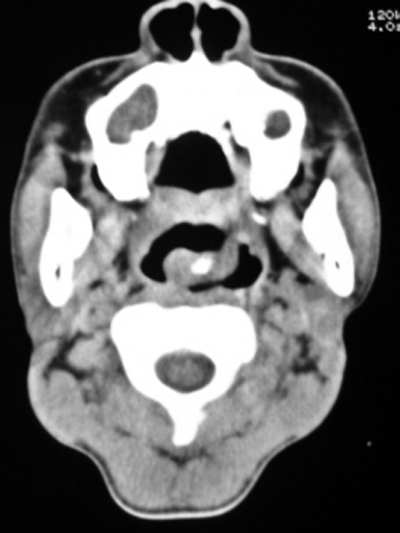

以下是引用随光逐影在2009-4-23 19:35:00的发言:[br]1)鼻咽、口咽、左侧鼻腔及右侧鼻后孔处新生物,考虑息肉可能性大。2)双侧上颌窦及双侧筛窦炎症,不排除双侧上颌窦内息肉可能。

以下是引用syfszcw在2009-4-23 13:21:00的发言:[br]双侧上颌窦 筛窦慢性炎症,鼻息肉 会厌ca[br][br][本贴已被 syfszcw 于 2009-4-23 13:36:46 修改过]

以下是引用bmw011在2009-4-23 13:23:00的发言:[br]考虑鼻息肉,上颌窦、筛窦炎